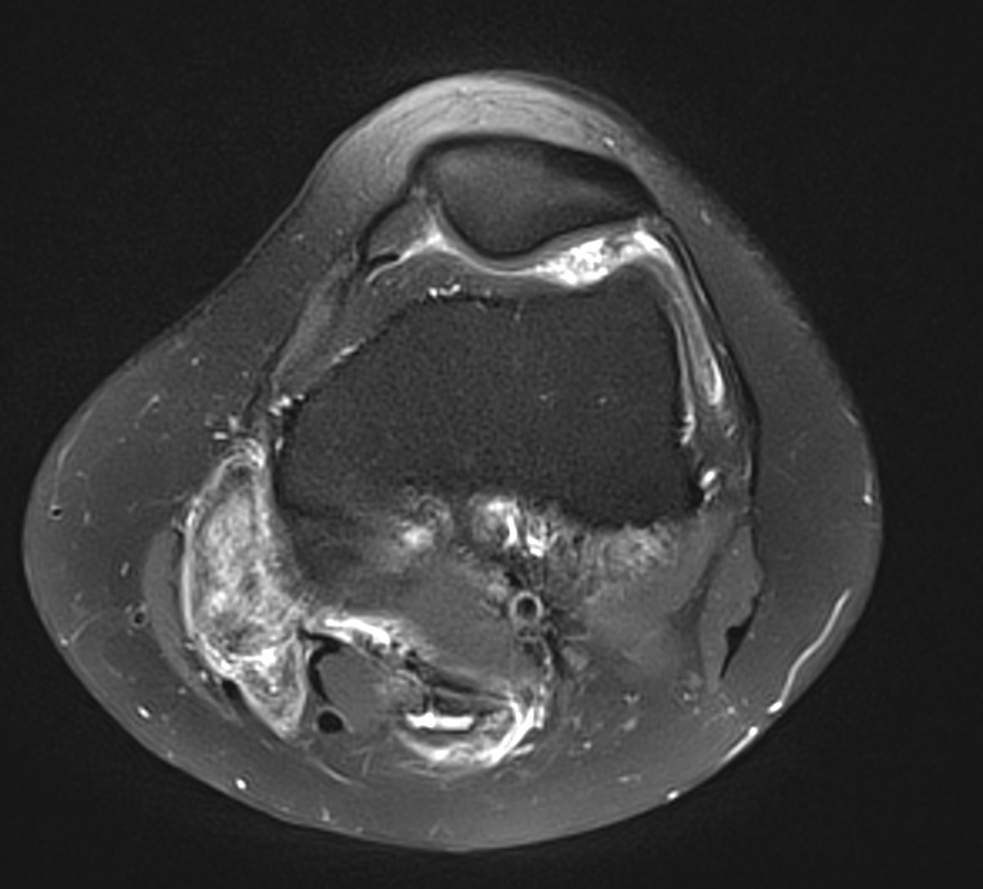

Synovite villo-nodulaire du genou